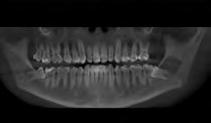

This past summer, the team at Shadow Mountain Dental Group treated a 16-year-old patient who initially came in for a routine exam. During the exam, he shared he had been experiencing slight discomfort on the lower side which he thought might have been coming from his wisdom tooth. After reviewing the patient’s pano and X-rays, Owner Dentist Ali Shahrestani, DMD, noticed a large radiolucency on the lower left side mandible and ordered a CBCT to see the lesion in more detail.

“My initial deferential diagnosis was odontogenic keratocyst, ameloblastoma or glandular cyst, so I referred the patient to an oral surgeon who decided to remove all the wisdom teeth and explore the radiolucency once he removed tooth #17,” said Dr. Shahrestani. “After the tooth was removed, the area was explored and it was determined that the radiolucency was just airspace. No further treatment was necessary.”

What makes this case unique is that CBCT’s powerful technology gives clinicians a clearer view of what may be going on in a patient’s mouth. It can also help give patients the peace of mind they need.

“Knowing there was no abnormality, the patient and his parents were grateful for this technology to complete the exam,” explained Dr. Shahrestani. “In reviewing this case, I’m convinced that taking a CBCT on younger patients is imperative and with the digital technology that we have today, radiation is very minimal and the benefits outweigh the risks. In my opinion we should be taking CBCT on every patient 16 years of age and older at least once a year.”